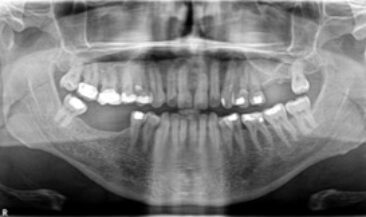

Sinus lift & block graft reconstruction